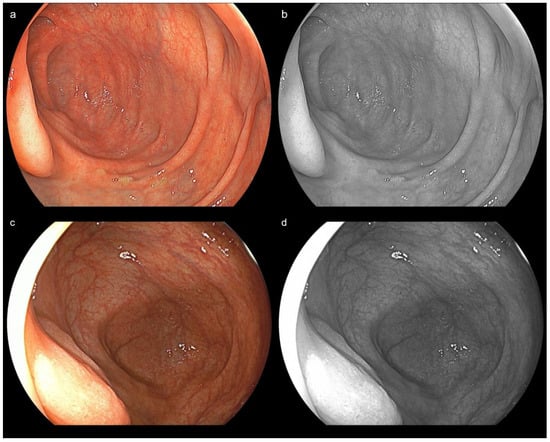

- Yoshida, N.; Hayashi, Y.; Kashida, H.; Tomita, Y.; Dohi, O.; Inoue, K.; Hirose, R.; Itoh, Y.; Okada, M.; Yoshimoto, S.; et al. Images of laser and light-emitting diode colonoscopy for comparing large colorectal lesion visibility with linked color imaging and white-light imaging. Dig. Endosc. 2022, 34, 1413–1421. [Google Scholar] [CrossRef]